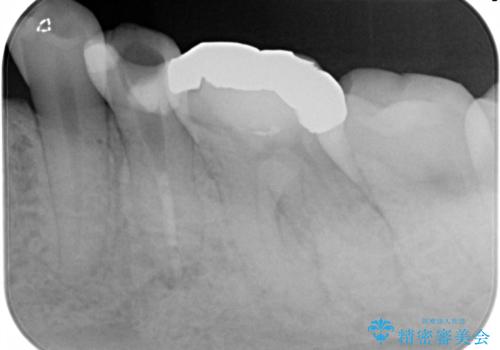

精密根管治療。大臼歯イニシャルケース

- 奥歯がズキズキ痛いことを主訴に来院されました。

検査の結果、診断を症候性不可逆性歯髄炎、症候性根尖性歯周炎とし抜髄を行っております。

根管充填はCWCTにて行なっております。

根管形成はマルテンサイト相を有するNi-Tiロータリーファイル(NEX MS)使用。